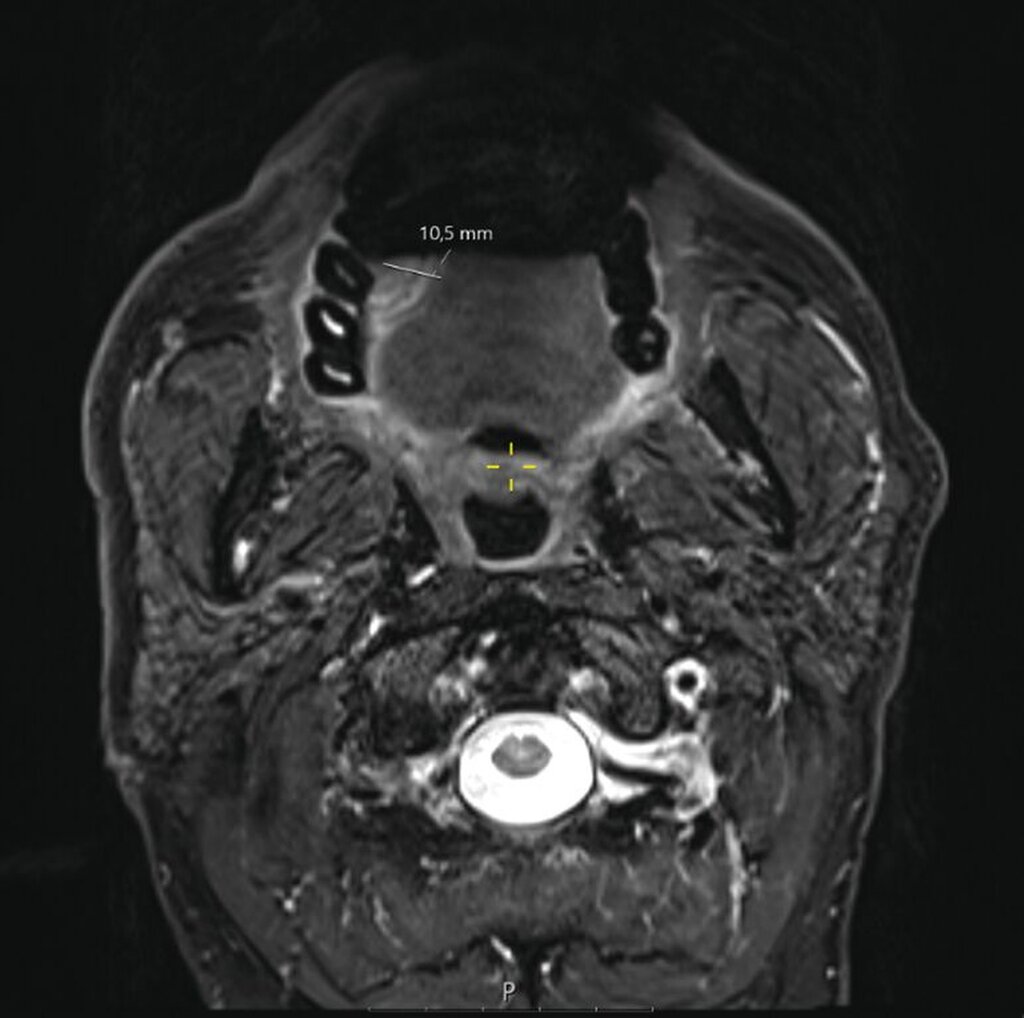

Ein Jahr später, im Februar 2025, stellte sich der Patient nach frustraner alternativmedizinischer Therapie erneut in der Universitätsklinik vor. Klinisch bestand nun eine deutliche Größenzunahme mit Annäherung an die Mittellinie (Abbildung 2). Die durchgeführte Bildgebung mittels MRT war aufgrund großer Ausleuchtungsartefakte der Zahnprothetik nur teilweise verwertbar. Allerdings zeigte sich der beschriebene Befund in T1-Richtung mit einer Tumordicke von circa 10 mm und einer Infiltrationstiefe von 5 mm (Abbildung 3).